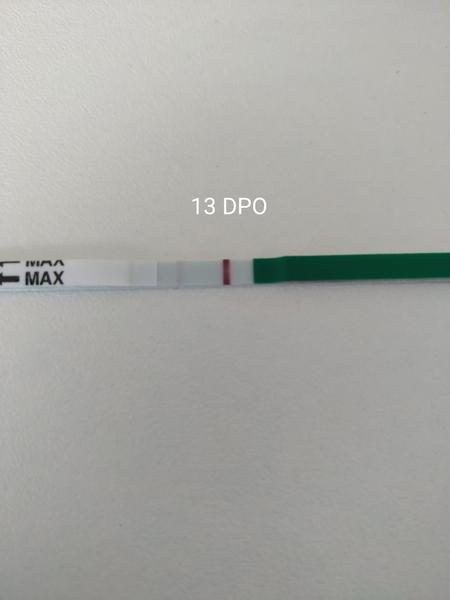

- Digitální těhotenské testy (např. Clearblue) zobrazují odhad stáří jako "+1-2", "+2-3" nebo "3+", ale výsledky závisí na citlivosti testu a hladině hCG v moči.

- Při slabém pozitivním proužku se doporučuje opakované kvantitativní vyšetření hCG v krvi (odebírání s odstupem ~48 hodin) pro zjištění trendu růstu a vyloučení biochemického nebo mimoděložního těhotenství.

A: Biochemické těhotenství je počínající těhotenství, které se neuchytí správně a skončí s menstruací; v diskuzi je popsáno jako slabé pozitivum na močovém testu a nízké nebo pomalu rostoucí hladiny hCG v krvi.

A: V diskuzi se uvádí, že u normálně se vyvíjejícího těhotenství by se měla hladina hCG zhruba zdvojnásobit každých 48 hodin; pokud hCG neroste tímto tempem, doporučuje se opakované kvantitativní odběry krve, protože tento obraz může naznačovat selhání těhotenství nebo mimoděložní těhotenství.

A: Uživatelé radí používat stále stejnou značku testů (např. mamatest comfort) pro srovnatelnost, protože různé testy mají odlišné barviva a citlivosti (v diskuzi zmíněna "citlivost 25"); při pochybnostech doporučují kvantitativní krevní test hCG.

- Opakované kvantitativní vyšetření hCG v krvi je doporučováno při slabých pozitivních močových testech.

- Někteří účastníci tvrdí, že slabé pozitivum a pomalé stoupání hCG nejčastěji znamená biochemické nebo neudržitelné těhotenství, zatímco jiní uvádějí případy, kdy slabé čárky nebo nízké hodnoty hCG vedly k normálnímu pokračujícímu těhotenství.